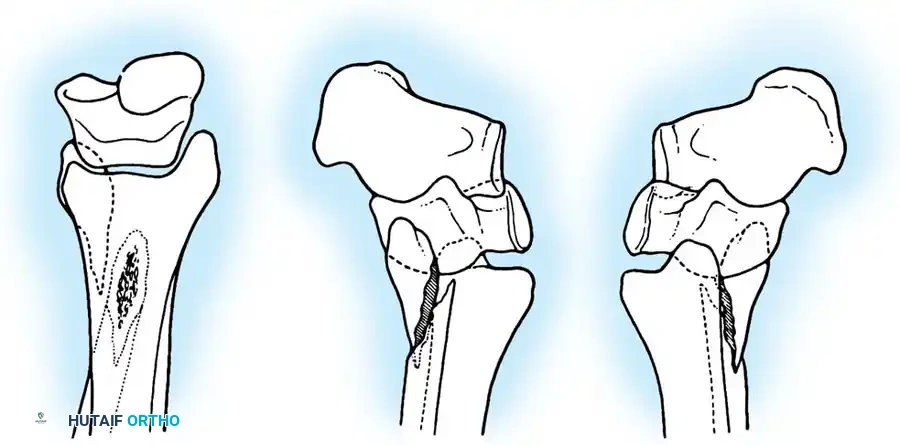

Danis-Weber Classification

The Danis-Weber classification is based purely on the anatomic location of the fibular fracture relative to the syndesmosis. It is highly practical for determining the likelihood of syndesmotic instability.

- Type A: Fibula fracture below the syndesmosis (infrasyndesmotic). The syndesmosis is intact. Correlates with Lauge-Hansen SA.

- Type B: Fibula fracture at the level of the syndesmosis (transsyndesmotic). The syndesmosis may or may not be torn. Correlates with Lauge-Hansen SER. Approximately 80% to 90% of lateral malleolar fractures fall into this category.

- Type C: Fibula fracture above the syndesmosis (suprasyndesmotic). The syndesmosis is invariably disrupted. Correlates with Lauge-Hansen PER or PA.

- Buttress Plating: Vertical shear fractures (characteristic of SA injuries) require horizontally directed screws or, more reliably, a small semitubular buttress plate applied to the medial apex to resist vertical displacement.